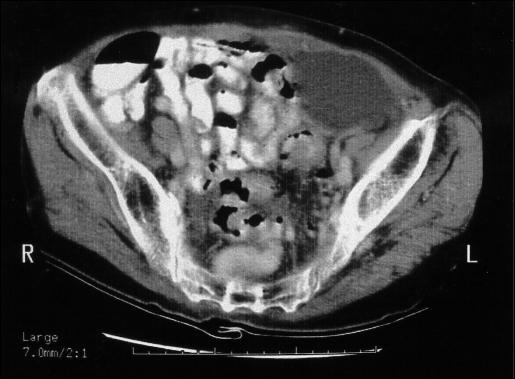

Painful preperitoneal collection is a rare complication following endoscopic totally extraperitoneal inguinal hemioplasty. Here we present the case of a woman who underwent endoscopic extraperitoneal inguinal hernioplasty for a left inguinal hernia. Her past health was good. During the dissection of the extraperitoneal space, clear ascitic fluid was noted upon breaching the peritoneum near the round ligament. Endoscopic stapling was used to close the peritoneal tear, and the procedure was completed uneventfully. The patient complained of left iliac pain after the operation. A physical examination showed no swelling over the left iliac fossa. Contrast computed tomography of the abdomen revealed preperitoneal fluid collection over the hernioplasty site and a small amount of ascites. Expectant treatment with pain control by oral analgesics was adopted. A follow-up CT scan 4 months after the operation showed resolution of the preperitoneal fluid collection but with increased ascites. Abdominal paracentesis with peritoneal fluid for cytology analysis found adenocarcinoma cells. The patient succumbed to a terminal malignancy a year after surgery. Conversion of endoscopic extraperitoneal inguinal hernioplasty to open repair should be considered upon intraoperative discovery of ascites. Painful preperitoneal collection is a possible sequela following endoscopic extraperitoneal hernioplasty in patients with malignant ascites.

疼痛性腹膜前积液是内镜下完全腹膜外腹股沟疝修补术后一种罕见的并发症。在此,我们报告一例接受内镜下腹膜外腹股沟疝修补术治疗左侧腹股沟疝的女性病例。她既往健康状况良好。在腹膜外间隙分离过程中,在靠近圆韧带处突破腹膜时发现清亮腹水。采用内镜下吻合器闭合腹膜撕裂口,手术顺利完成。术后患者诉左髂部疼痛。体格检查显示左髂窝无肿胀。腹部增强CT显示疝修补部位腹膜前积液及少量腹水。采取口服镇痛药控制疼痛的保守治疗。术后4个月的随访CT扫描显示腹膜前积液消失,但腹水增多。经腹穿刺抽取腹水进行细胞学分析发现腺癌细胞。患者术后一年死于终末期恶性肿瘤。术中发现腹水时应考虑将内镜下腹膜外腹股沟疝修补术转为开放修补。对于合并恶性腹水的患者,疼痛性腹膜前积液是内镜下腹膜外疝修补术后可能出现的后遗症。